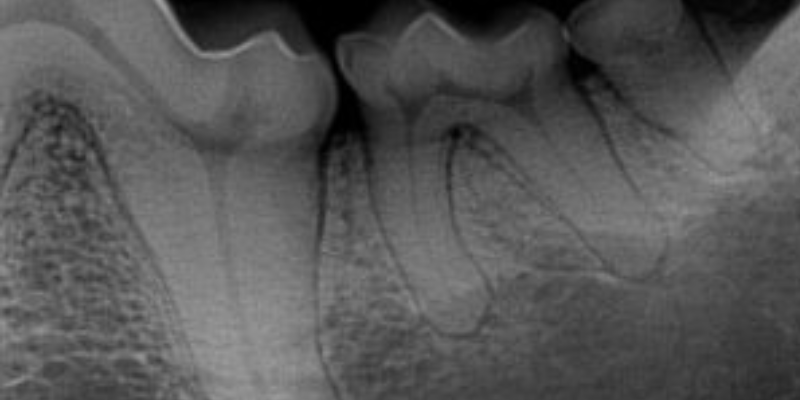

Dr. Elizabeth Brine is one of our board-certified veterinary dentists. She has advanced training and specialist certification in dentistry. She recalls the story of a dog whose outward behavior became aggressive due to dental pain. The dog’s owner insisted her twelve-year-old dog needed to be looked at for a dental problem. Five months earlier, the dog had a dental cleaning at the family veterinarian, but not dental x-rays. The issue wasn’t resolved, and the dog was now fighting other dogs in the house. Dr. Brine’s examination and all the blood work seemed to be normal. Dr. Brine x-rayed the dog’s mouth and the problem was found. She discovered wide swellings around the tooth roots of both lower first molars. It was a hidden and painful problem that wouldn’t have been discovered if the owner hadn’t insisted upon seeing a veterinary dentist.